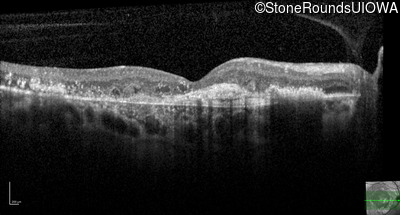

Age at visit: 59 years (Visit 3)